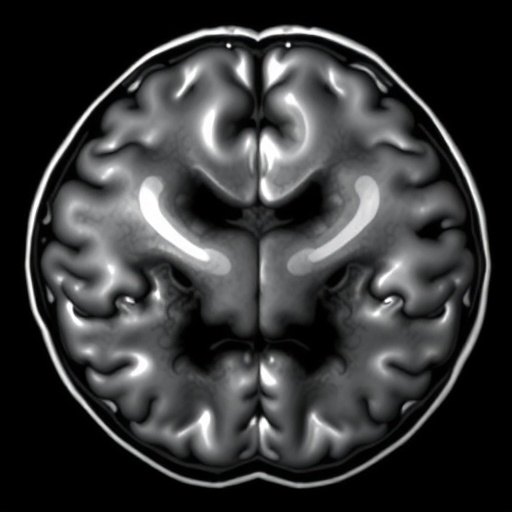

In the ever-evolving landscape of medical imaging, the need for precise and efficient segmentation of brain tumors from MRI scans has never been more critical. With the prevalence of various types of brain tumors, early diagnosis and effective treatment planning hinge on high-quality imaging modalities. A recent survey conducted by Yang et al. sheds light on U-Net variant networks, which have garnered attention for their striking effectiveness in segmenting brain tumors from MRI scans. This exploration highlights not just advancements in technology but also the collaborative efforts that are pushing the boundaries of medical research.

The U-Net architecture, initially designed for biomedical image segmentation, has emerged as a cornerstone in various medical imaging applications. Its unique structure—a contracting path that captures context and a symmetric expanding path that enables precise localization—has made it particularly adept at handling the complexities of MRI scans. The architecture facilitates multi-scale feature extraction, which is essential when dealing with the diverse presentations of brain tumors in patients. As Yang and his colleagues delve into the various adaptations of this architecture, it becomes apparent that understanding these modifications is crucial for future advancements in the field.